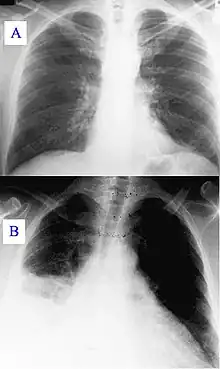

- Pneumonie :

- une imagerie est nécessaire pour poser le diagnostic[19]. Il se base sur la présence d'un infiltrat alvéolaire ou bronchogramme aérique ;

- suspicion étiologique : une pneumonie lobaire est plus facilement bactérienne ; une lésion caverneuse apicale est suspecte de tuberculose ; un infiltrat diffus est suspect de pneumonie virale ;

- complication : principalement l’épanchement pleural ;

- évaluation de la sévérité : une pneumonie multi-lobaire étendue ou bilatérale indique, associée à d'autres critères (hypotension, hypoxémie, urémie), une mortalité plus élevée et nécessite une hospitalisation en soins intensifs[20] ;

- Pneumothorax, hémothorax, chylothorax

- Décompensation cardiaque

Ceux-ci sont souvent décrits, enseignés dans les facultés de médecine[29],[30],[31],[32] et en soins infirmiers[33]. La littérature qui sous-tend toutes ces descriptions est ancienne à très ancienne[34],[35].- Signe en faveur d'une décompensation du « cœur droit » :

- épanchement pleural à droite, multifactoriel, peut être lié à la présence d'ascite sur congestion hépatique chronique ou à l'obstruction du retour veineux des bronches et des lymphatiques pulmonaires (ceux-ci, à cause de la surcharge ne pouvant se drainer dans les veines azygos et hémi-azygos[36]),

- épanchement pleural.